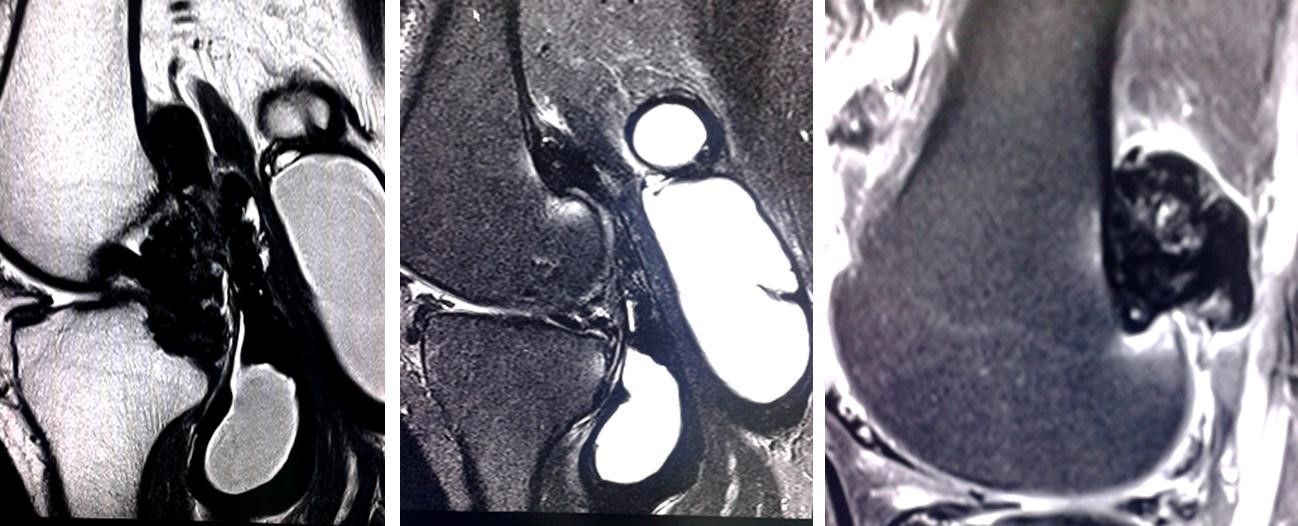

Volver a los detalles del artículo Sinovitis vellonodular pigmentada difusa